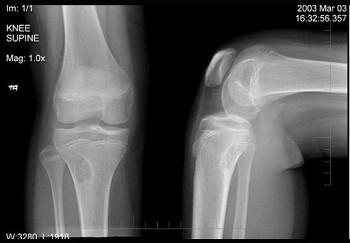

问题 左膝关节酸胀不适,摄片发现左胫骨上段局限性骨质改变如图示,最可能的诊断是 ( )

选项 A、骨软骨瘤 B、骨肉瘤 C、骨化性纤维瘤 D、内生软骨瘤 E、非骨化性纤维瘤

答案 E